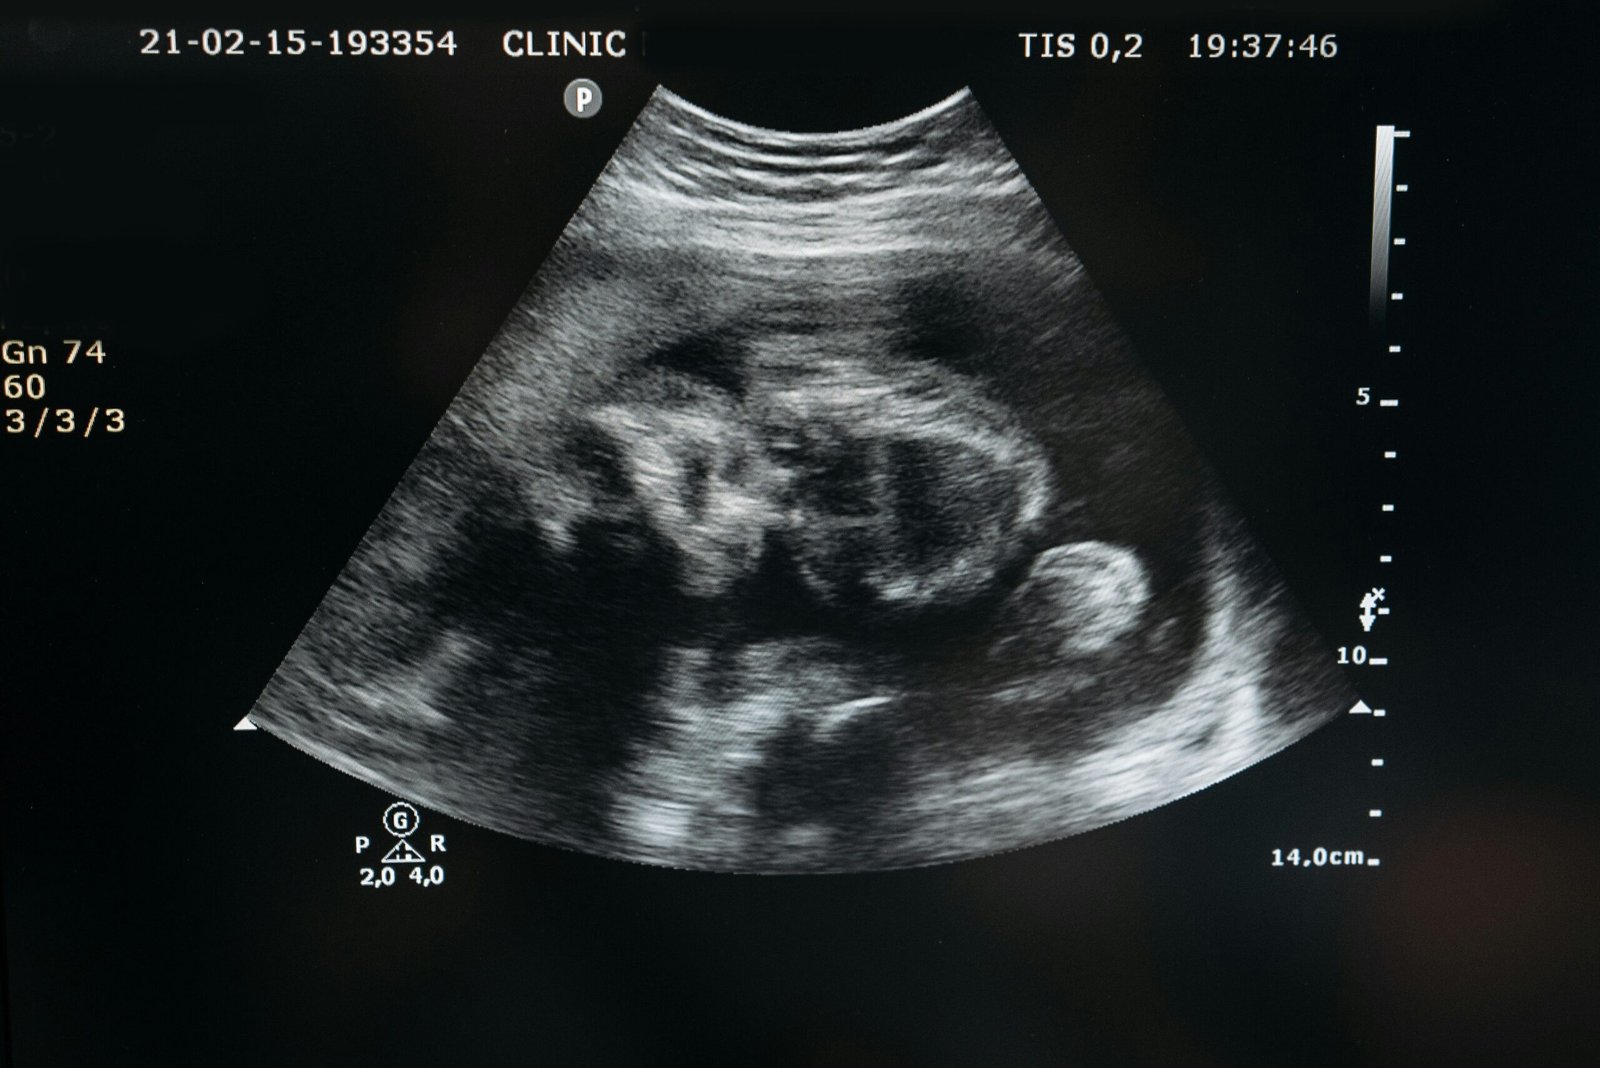

Sonografia Morfologica

La sonografía morfológica es una ecografía detallada que se realiza entre las semanas 18 y 22 del embarazo para evaluar la anatomía del bebé y detectar posibles malformaciones.

En NatalMedica, este estudio se realiza con precisión y sensibilidad clínica, pero lo que realmente distingue al centro es su compromiso con la prevención activa, el seguimiento personalizado y su enfoque en el bienestar integral de la madre y el bebé, más allá del diagnóstico.